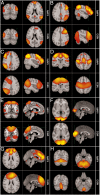

In recent years the study of resting state brain networks (RSNs) has become an important area of neuroimaging. The majority of studies have used functional magnetic resonance imaging (fMRI) to measure temporal correlation between blood-oxygenation-level-dependent (BOLD) signals from different brain areas. However, BOLD is an indirect measure related to hemodynamics, and the electrophysiological basis of connectivity between spatially separate network nodes cannot be comprehensively assessed using this technique. In this paper we describe a means to characterize resting state brain networks independently using magnetoencephalography (MEG), a neuroimaging modality that bypasses the hemodynamic response and measures the magnetic fields associated with electrophysiological brain activity. The MEG data are analyzed using a unique combination of beamformer spatial filtering and independent component analysis (ICA) and require no prior assumptions about the spatial locations or patterns of the networks. This method results in RSNs with significant similarity in their spatial structure compared with RSNs derived independently using fMRI. This outcome confirms the neural basis of hemodynamic networks and demonstrates the potential of MEG as a tool for understanding the mechanisms that underlie RSNs and the nature of connectivity that binds network nodes.